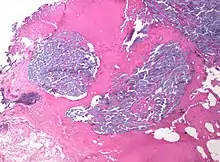

Desmoplasia refers to growth of dense connective tissue or stroma.[2] This growth is characterized by low cellularity with hyalinized or sclerotic stroma and disorganized blood vessel infiltration.[3] This growth is called a desmoplastic response and occurs as result of injury or neoplasia.[2] This response is coupled with malignancy in non-cutaneous neoplasias, and with benign or malignant tumors if associated with cutaneous pathologies.[3]

A desmoplastic response is characterized by larger stromal cells with increased extracellular fibers and immunohistochemically by transformation of fibroblastic-type cells to a myofibroblastic phenotype.[2] Myofibroblastic cells in tumors are differentiated from fibroblasts for their positive staining of smooth-muscle actin (SMA).[2] Furthermore, an increase in total fibrillar collagens, fibronectins, proteoglycans, and tenascin C are distinctive of the desmoplastic stromal response in several forms of cancer.[14] Expression of tenascin C by breast cancer cells has been demonstrated to allow for metastasis to the lungs and cause the expression of tenascin C by the surrounding tumor stromal cells.[15] In addition, tenascin C is found extensively in pancreatic tumor desmoplasia as well.[16]

Differentiation of scars

While scars are associated with the desmoplastic response of various cancers, not all scars are associated with malignant neoplasms.[3] Mature scars are usually thick, collagenous bundles arranged horizontally with paucicellularity, vertical blood vessels, and no appendages.[3] This is distinguished from desmoplasia in the organization of the tissue, the appendages, and orientation of blood vessels. Immature scars are more difficult to distinguish due to their neoplastic origins.[3] These scars are hypercellular with fibroblasts, myofibroblasts, and some immune cells present.[3] The immature scars can be distinguished from desmoplasia by immunohistochemical staining of biopsied tumors that will reveal the type and organization of cells present as well as whether recent trauma has occurred to the tissue.[17]